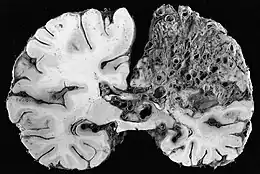

- angiome caverneux (ou « cavernome cérébral ») ; malformation vasculaire située en grande partie dans le cerveau, généralement non détectée, sauf lorsqu'elle cause des crises convulsives ou des hémorragies cérébrales (fréquence : 1 sujet sur 1 000, avec forme familiale dans 20 % des cas). Trois gènes situés sur les chromosomes 7 et 3 semblent impliqués ;